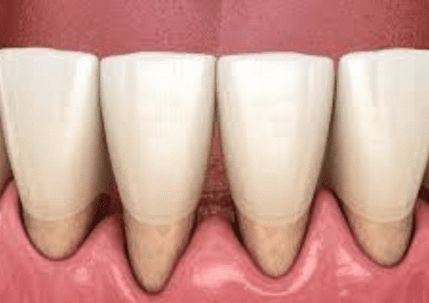

Because tooth decay has numerous stages, there are a variety of symptoms that you may see, feel, or even taste at times. The treatment you will require for your cavity will be determined by how serious the decay is and where it is located. Stage 1: The enamel is decaying. A cavity has not yet passed through the enamel, which is the outer coating of the tooth, during its early stages. During this period, symptoms are not very severe. In fact, you might not notice any of them at all. Sometimes, you may notice that your tooth has darkened, or you may feel a little sensitivity. Our Summerlin dentist will remove the area that has enamel decay and fill the empty space with a tooth-colored filling material in order to repair the decay. Fillings are a quick and inexpensive option that can last for many years. Stage 2: Dentin After the decay has passed through the enamel surface, it will reach the dentin layer. The dentin layer is fragile and is particularly susceptible to decay. This means that if the cavity reaches the dentin, it can spread quickly. During this stage, you will notice that your tooth sensitivity is more pronounced. You might feel uncomfortable when you eat sweets, clean your teeth, or are in chilly conditions. If the decay has impacted much of your tooth, our dentist in Summerlin may suggest that you get a crown instead of a filling. A crown is a hard cap that goes over your tooth and protects it from further harm. Because this treatment is more complex, it does take longer to finish. Additionally, it is more expensive than simply a basic filling. However, if crowns are manufactured and maintained correctly, they can last for many years, making your investment worthwhile. Stage 3: Pulp Chamber The decay will enter the pulp chamber once it has passed through the dentin layer. This is the section of the tooth that has blood arteries, nerves, and connective tissue. Your tooth will become infected after the cavity has reached the pulp. You will go through a lot of discomfort during this time. You may also start to feel uncomfortable due to heat, in addition to chilly weather. You may also experience persistent discomfort that necessitates the use of pain medication to alleviate it. We will take an x-ray of your tooth to make sure that the cavity has reached the pulp chamber. Root canal therapy will be necessary to fix and protect your tooth. This surgery consists of taking out the nerve tissue, cleaning the canals, and closing them off in order to stop bacteria from coming back in. You will probably need to be fitted for a crown in addition to receiving therapy on the nerves of your tooth. This will help to prevent additional harm to the tooth that is already at risk. Stage 4: Abscess The roots of your teeth are the parts that you cannot see when you look inside your mouth. They are located in the jaw. Nerve channels that go down each root extend beyond the pulp chamber. If your cavity has reached the nerves in the root of your tooth, you may have a terrible pain and swelling in your face. If you have an abscess, you will see a little bump on your gums, which is called a fistula. A dental abscess is a major medical issue. You might not find any relief from over-the-counter pain drugs. The toothache could prevent you from sleeping at night or cause you to wake up often. The gum tissue surrounding the tooth that is impacted may swell, and this swelling could migrate to your face. You might possibly develop a fever. If a cavity has caused a serious infection, it may not be possible to salvage the tooth with a root canal. It may be essential to do an extraction. We will be able to determine the state of your tooth and if it can be saved by using a dental x-ray. If it turns out that we need to take it out, a dental implant or a bridge could be a good option for you to replace it. Preventing Cavities Maintaining excellent dental hygiene is the most effective approach to avoid cavities. Make sure to have frequent cleanings and check-ups with your dentist in Las Vegas so that any problems can be addressed as soon as they arise. If you haven't gone to the dentist in a while or think you might have a cavity, you should make an appointment with Dr. Cohan at Summerlin Dental Solutions. Make an appointment by calling or book online today. GET TO KNOW YOUR BEST DENTIST IN SUMMERLIN